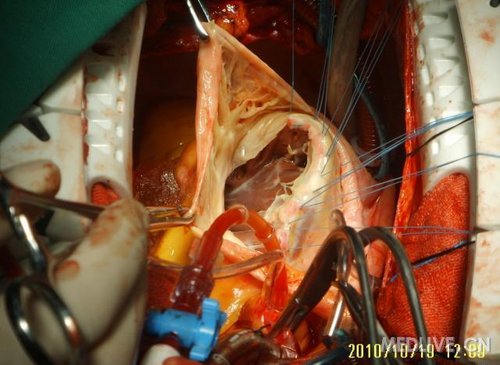

因这个患者三尖瓣存在明显器质性病变,遂采取了三尖瓣置换术。

切除三尖瓣瓣膜后,预置缝线

http://webres.medlive.cn/upload/000/060/752

这例患者选择了牛心包生物瓣膜,现门诊随访效果良好。